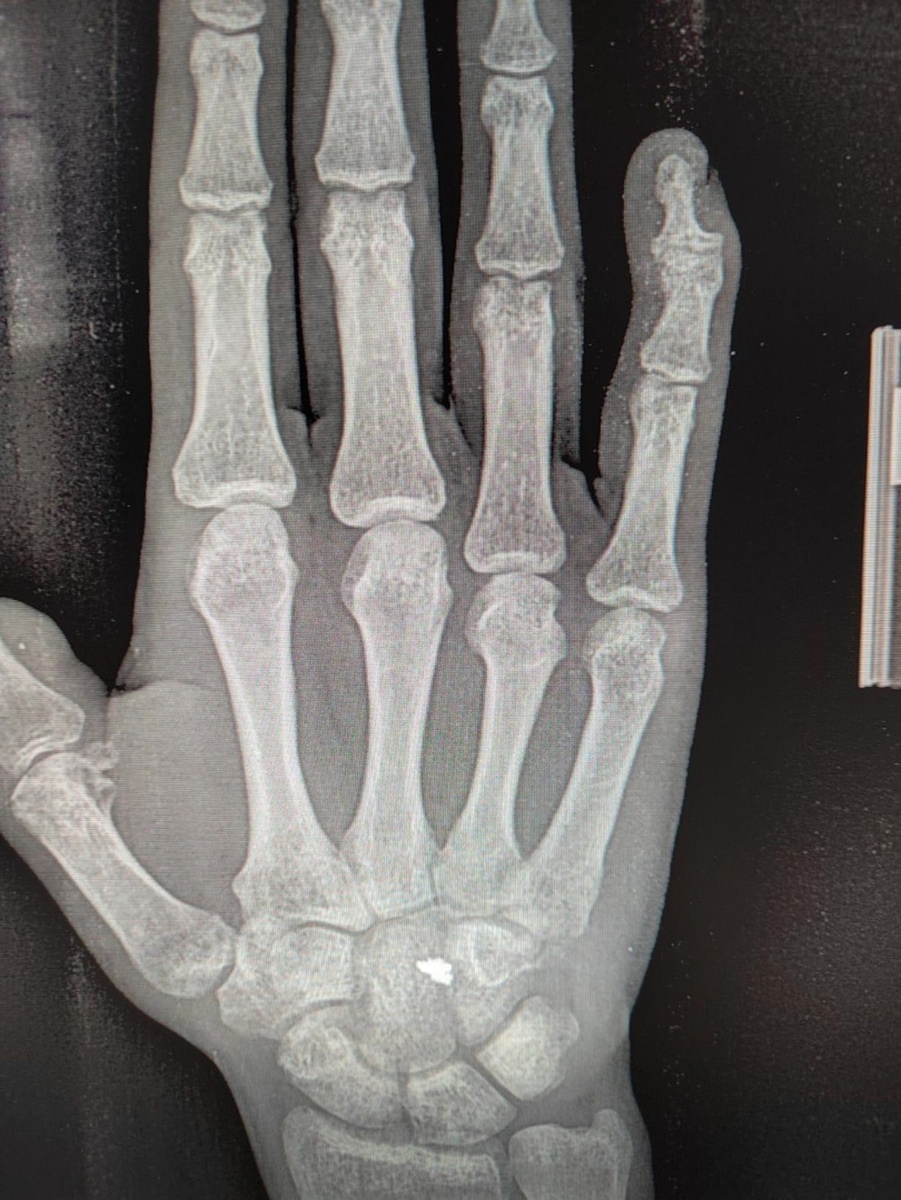

Поранил я руку в Ташкенте, случайно вышло, и очень быстро, в больнице экстренной медицины , Мне зашили рану и остановили кровотечение, Сказали, что потребуется операция, чтобы сшить сухожилия и нервные окончания. Через два дня, мы полетели домой в Солт Лейк Сити, По прилету , жена созвонилась с семейным доктором , и она направила нас к хирургу, который специализируется на кистях рук, буквально на следующий день состоялся прием, Доктор с фамилией Инглиш, назначил операцию на следующий день, Операция прошла хорошо , после заживления раны, через неделю , виден был большой порез и швы, Еще через несколько дней доктор направил меня в реабилитационный центр к ортопеду, Там Она сняла швы, такие тоненькие лесочки с узелками, надрезала лесочку и за узелочек пинцетом вытягивала, было немного больно. После этого начались занятия. В первый прием, она наложила на мою руку, горячий пластмасс, он был мягким, она прижимая к моей руке эту массу, придала форму, и когда пластмасса застыла, получился